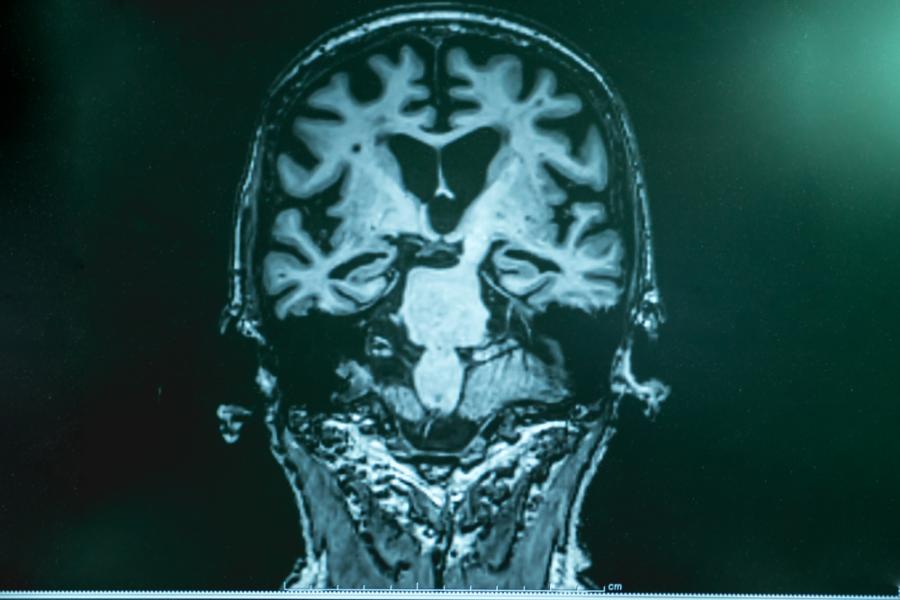

Според учените, това би обяснило произхода на малките черни плаки - мистериозни твърди малки топчета, които бележат като шарка мозъците на хората с такава диагноза.

Харвардските учени докладват за сценарий, който идва сякаш от научно-фантастичен филм. Вирус, гъбички или бактерии, се прокрадват в мозъка, преминават пред мембраната му - кръвно-мозъчната бариера, която става все по-пропусклива с напредването на възрастта. Отбранителната система на мозъка се впряга да спре нападателя като прави лепкава мрежа от протеини, наречени бета амилоид. Микробът, също както муха в мрежата на паяк, се хваща в примката и умира. Това, което остава в мрежата, е плаката, която е белегът на болест на Алцхаймер.